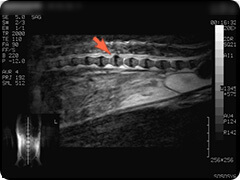

- 脊髄空洞症

- 脊髄内に空洞が生じた状態で、空洞内には脳脊髄液と同様の液体が満たされています。

疼痛がでたりふらつきや不全麻痺など症状は様々です。 -

頸部の脊髄です。水っぽいところが白く映っています。

水っぽいところは黒く映っています。